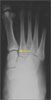

Anteroposterior radiographs of the right foot demonstrated a gap larger than 3 mm between the bases of the first and second metatarsals as well as between the first and second medial cuneiforms, with loss of alignment of the medial edge of the base of the second metatarsal with the medial edge of the medial cuneiform. This was a stage II sprain according to the Nunley and Vertullo classification.1 There was no fracture of the base of the second metatarsal.